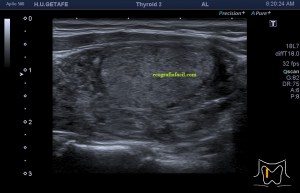

El paciente viene por un bulto en la parte derecha de la espalda, en la región paradorsal alta. Con una sonda de alta frecuencia accedo a la región, que era palpable. Lo primero que observo es que la transmisión del paciente no es buena, esto que a veces pasa que encuentras pacientes, que no sé explicar el motivo, no transmiten bien.

Me da para observar que en la zona de palpación encuentro, profundo en la imagen, un formación hiperecogénica, que está dentro de un músculo. Antes de detallar los hallazgos de la imagen lo que quise fue reconocer bien la anatomía. La piel y el tejido celular subcutánea era muy fácil, también saber que esta anatomía superficial estaba intacta y que la lesión estaba intramuscular, pero me encontraba dos planos musculares, uno superficial, el otro profundo, el profundo con la lesión.

El protocolo es el típico, cortes en eje corto y largo, con doppler, para comprobar vascularización, como línea roja del lipoma. Imágenes 3,4 y 6.

La lesión era ovalada, hiperecogénica, ocupaba gran parte del músculo, pero respetaba parte de este, que era hipoecogénico (imagen 5), recuerda que así es por definición y que ésta ecogenicidad del músculo es referencia para el resto de ecogenicidades del aparato locomotor. Como te he contado, no había doppler color ni en modo angio.